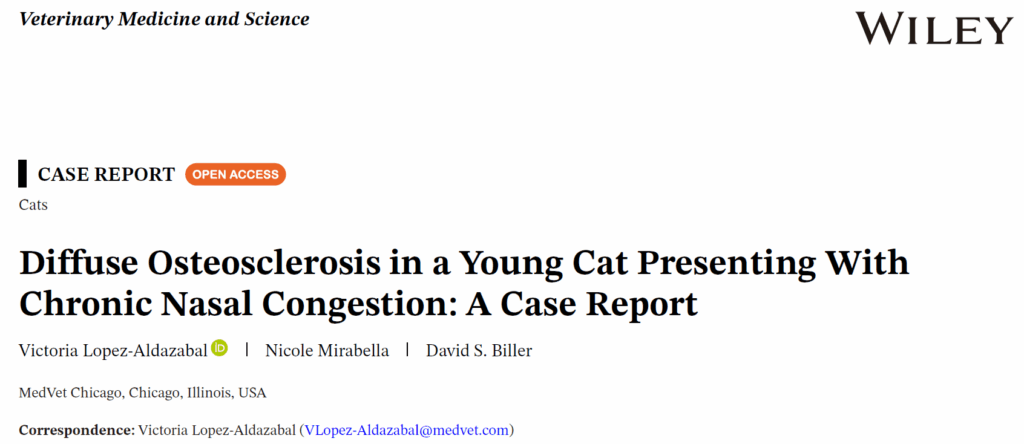

CT显示鼻甲骨弥漫性增厚、拥挤及密度增高,其骨密度接近皮质骨水平。鼻腔及额窦容积缩小(下图)。颅腔内神经组织未见异常。

↑ 第1行:鼻腔内严重弥漫性不规则骨质增生导致腔隙几乎完全闭塞。同时可见头部嵌入骨结构(如上颌骨、额骨、颧骨、腭骨及下颌骨)出现严重弥漫性硬化性增厚。第2行:可见所有骨结构均存在严重弥漫性硬化性增厚。鼻甲骨严重增厚,几乎完全阻塞鼻腔通道。